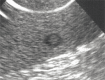

Aneurysm of the splenic artery (arrow)

Fig. 13 B